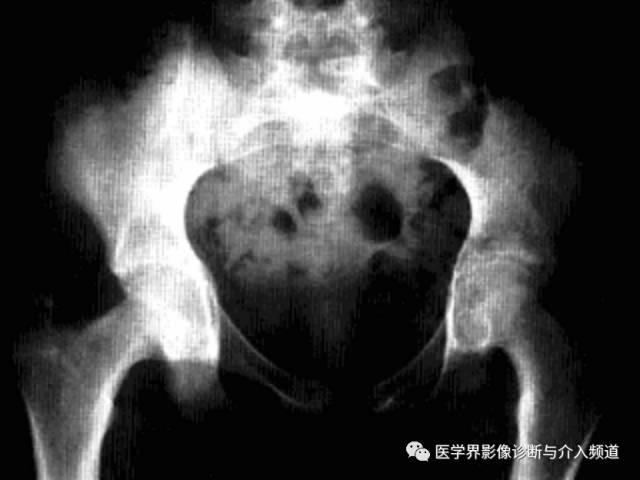

快速破坏性髋关节病

是一种不知确切病因而侵犯股骨头及髋臼导致髋关节在短时间内快速破坏的髋关节疾病。

临床表现:多发生于60岁以上老年女性,多一侧发病,无明显原因髋关节疼痛,之后逐渐加重,后期出现功能受限和跛行。

影像诊断:首选X线平片,髋关节正位及蛙氏位。

1、平片:髋关节间隙进行性消失是本病特征;早期股骨头无明显变化,数月间股骨头上方进展性破坏吸收,股骨头变扁,无囊变,骨赘增生不显著,周围软组织无明显异常。

2、CT:股骨头负重区骨质溶骨样改变,骨质碎裂的,关节面软骨大片状剥脱和皲裂,头中心骨质呈小圆形颗粒状改变,软骨下骨的连续性破坏,头外形不规则缺损,碎骨片线状分离。

3、MRI:股骨头及髋臼骨质吸收伴软骨丢失,股骨头向上外方移位,关节内积液,骨髓未见明显异常。